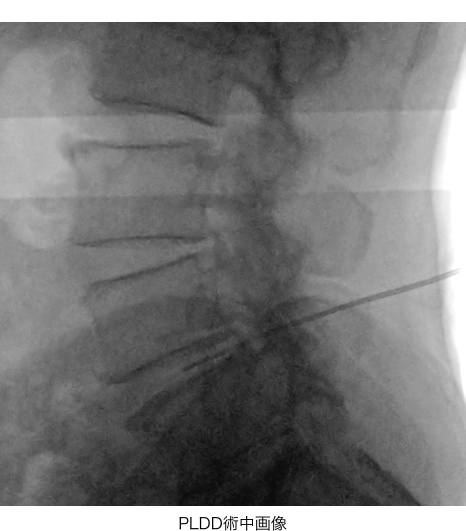

- PLDD(経皮的レーザー椎間板減圧術)

背中からレーザーファイバーが通った針を刺し、レーザーを照射してヘルニアの縮小を目指す「PLDD(経皮的レーザー椎間板減圧術)」を行いました。また、幹細胞を培養した溶液の上澄みである「幹細胞上清液」も投与しました。幹細胞上清液にはさまざまな成長因子が含まれており、組織の回復や症状の緩和を促進させる作用が期待できます。